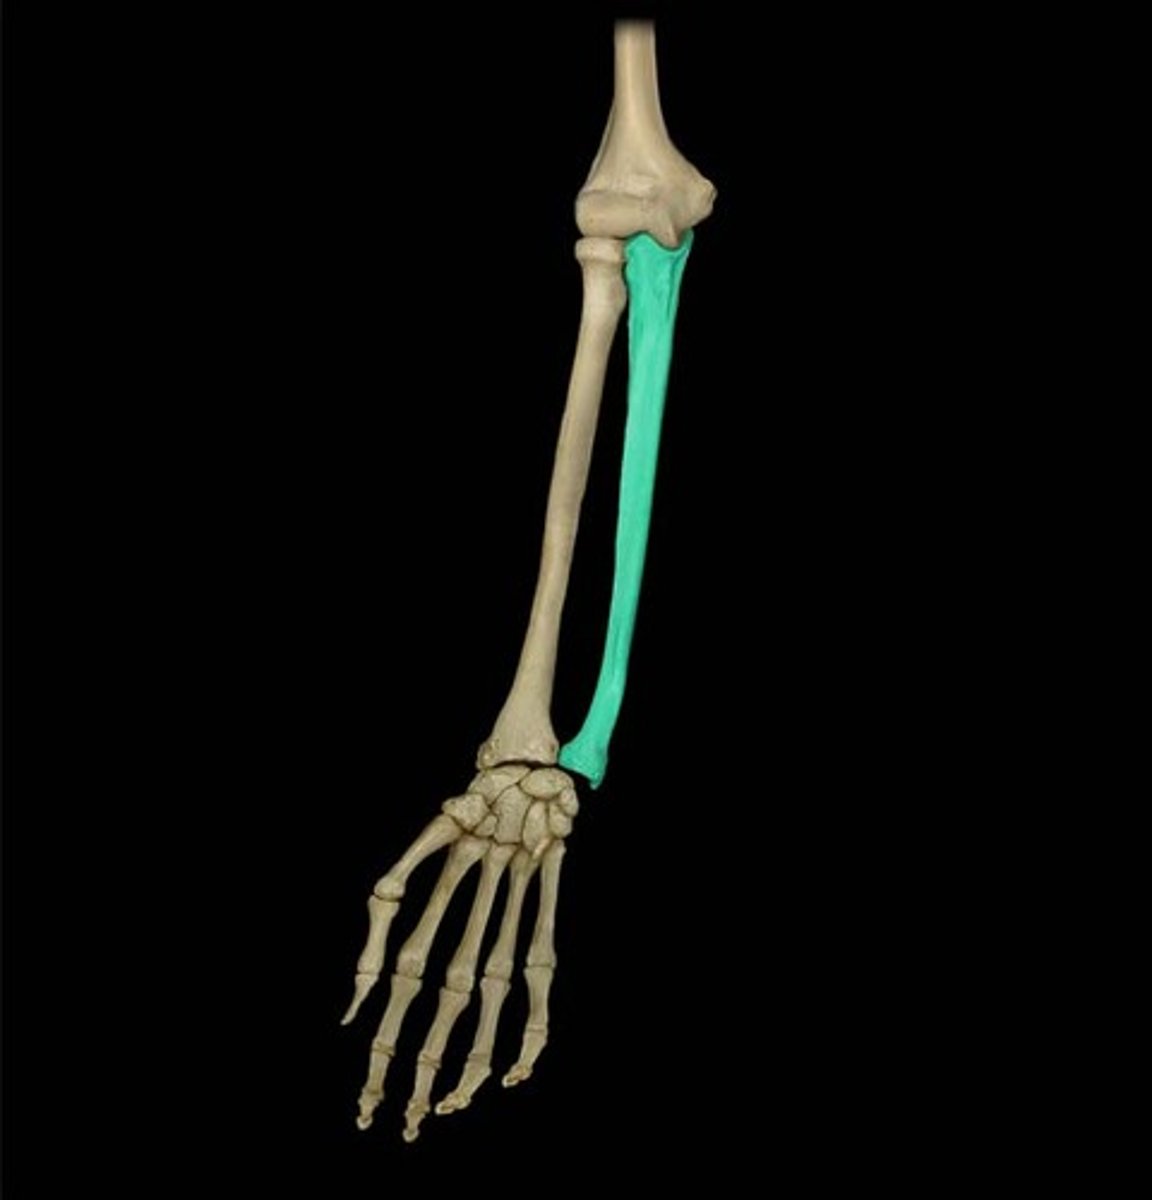

Bones of the forearm:

radius and ulna

Characteristics of the forearm:

- contains 2 bones

- radius can pivot on the ulna (supination and pronation) due to their parallel position

The ulna is the ___________ bone of the forearm

Stabilizing bone

Location of the ulna:

Medial and longer of the two forearm bones

What is the radius capable of doing?

Can pivot on the ulna (supination and pronation) due to their parallel position

Location of the radius:

Lateral & shorter of the forearm